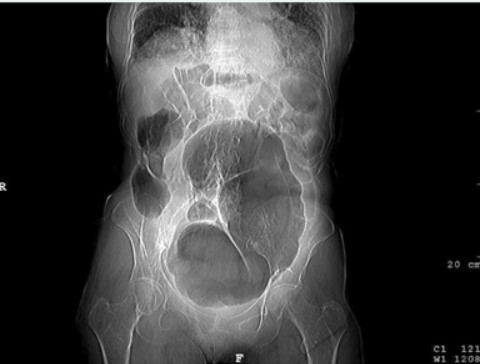

Vólvulo Cecal

• Estructura llena de aire en forma de riñón en Radiografia Abdominal